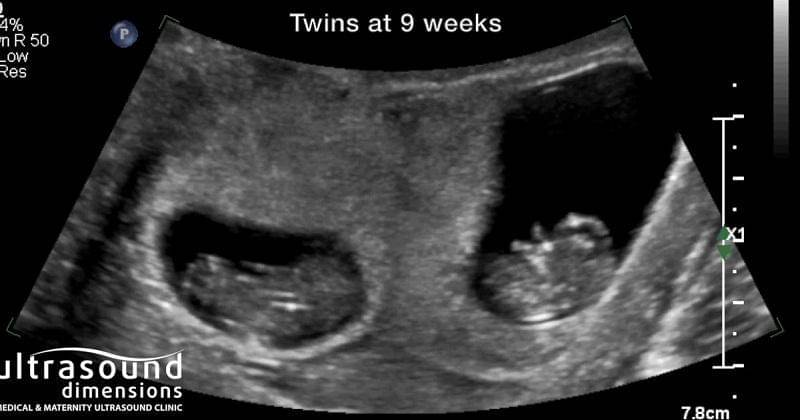

Itu dia tadi tanda hamil kembar di trimester pertama, Ma. Karena tanda-tandanya cenderung mirip dengan kehamilan satu janin, lebih baik melakukan USG untuk memastikan hamil kembar atau tidak.